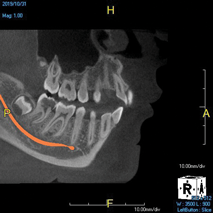

(7.) Treatment planning an implant case is made easier and more accurate by virtually placing implants of the chosen length and diameter and measuring the desired mesiodistal spacing prior to surgery.

Figure 7